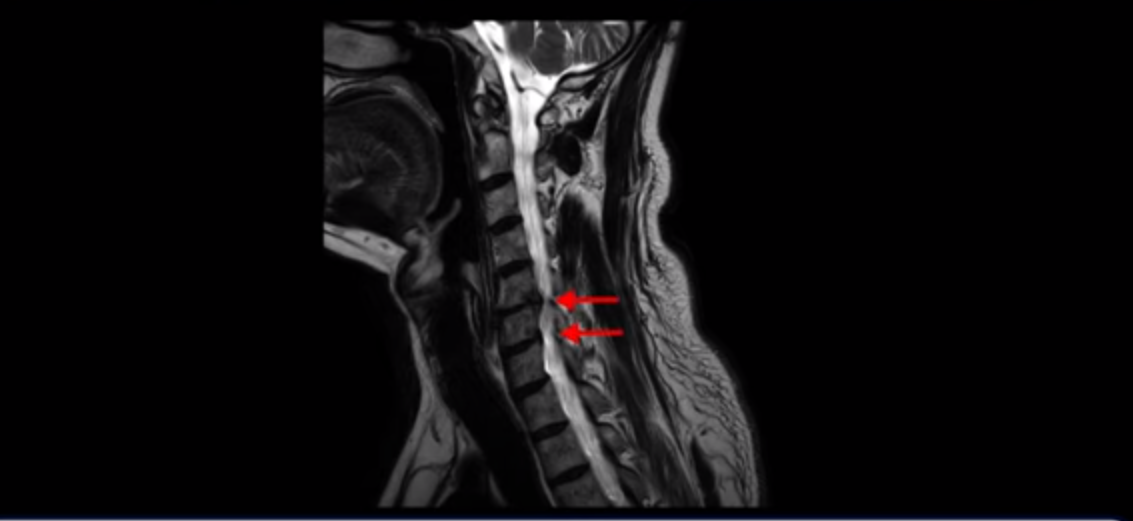

우선 이분 증상은 좌측 어깨와 팔 통증입니다. 이분 MRI를 보면 5번 6번과 6번 7번이 안 좋아 보입니다.

왼쪽으로 신경이 빠져나가는 추간공을 보면 보시다시피 5번 6번과 6번 7번 신경 구멍이 아래나 위에 비해 막혀있는 게 보입니다.

디스크도 밀려 나와 있고 협착도 있는 겁니다.

이분 왼쪽 어깨와 팔 통증이 갑자기 생긴 이유는 5번 6번 디스크 또는 6번 7번 디스크가 갑자기 밀려 나온 것이 원인일 것으로 보이는데, 그럼 이 디스크들이 밀려 나와서 신경을 자극하거나 누르는데 어떻게 이게 수술 없이도 좋아질 수 있는 걸까요?